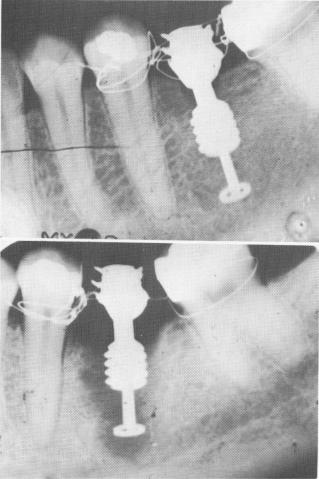

Fig. 14-34. A, Another single tooth implant, stabilized only by wiring to neighboring teeth. B, A few months later, the mobility allowed by this method has caused a great deal of bone resorption.

Fig. 14-35. Cements, whether of a temporary or more permanent type, should never be used inside the crown that covers the implant. In this case, the cement stuck to the implant post, pulling it out with the splint.

1 Single tooth implant, stabilized only by wiring to neighboring teeth

2 Cement stuck to maxillary implant post, pulling it out with splint